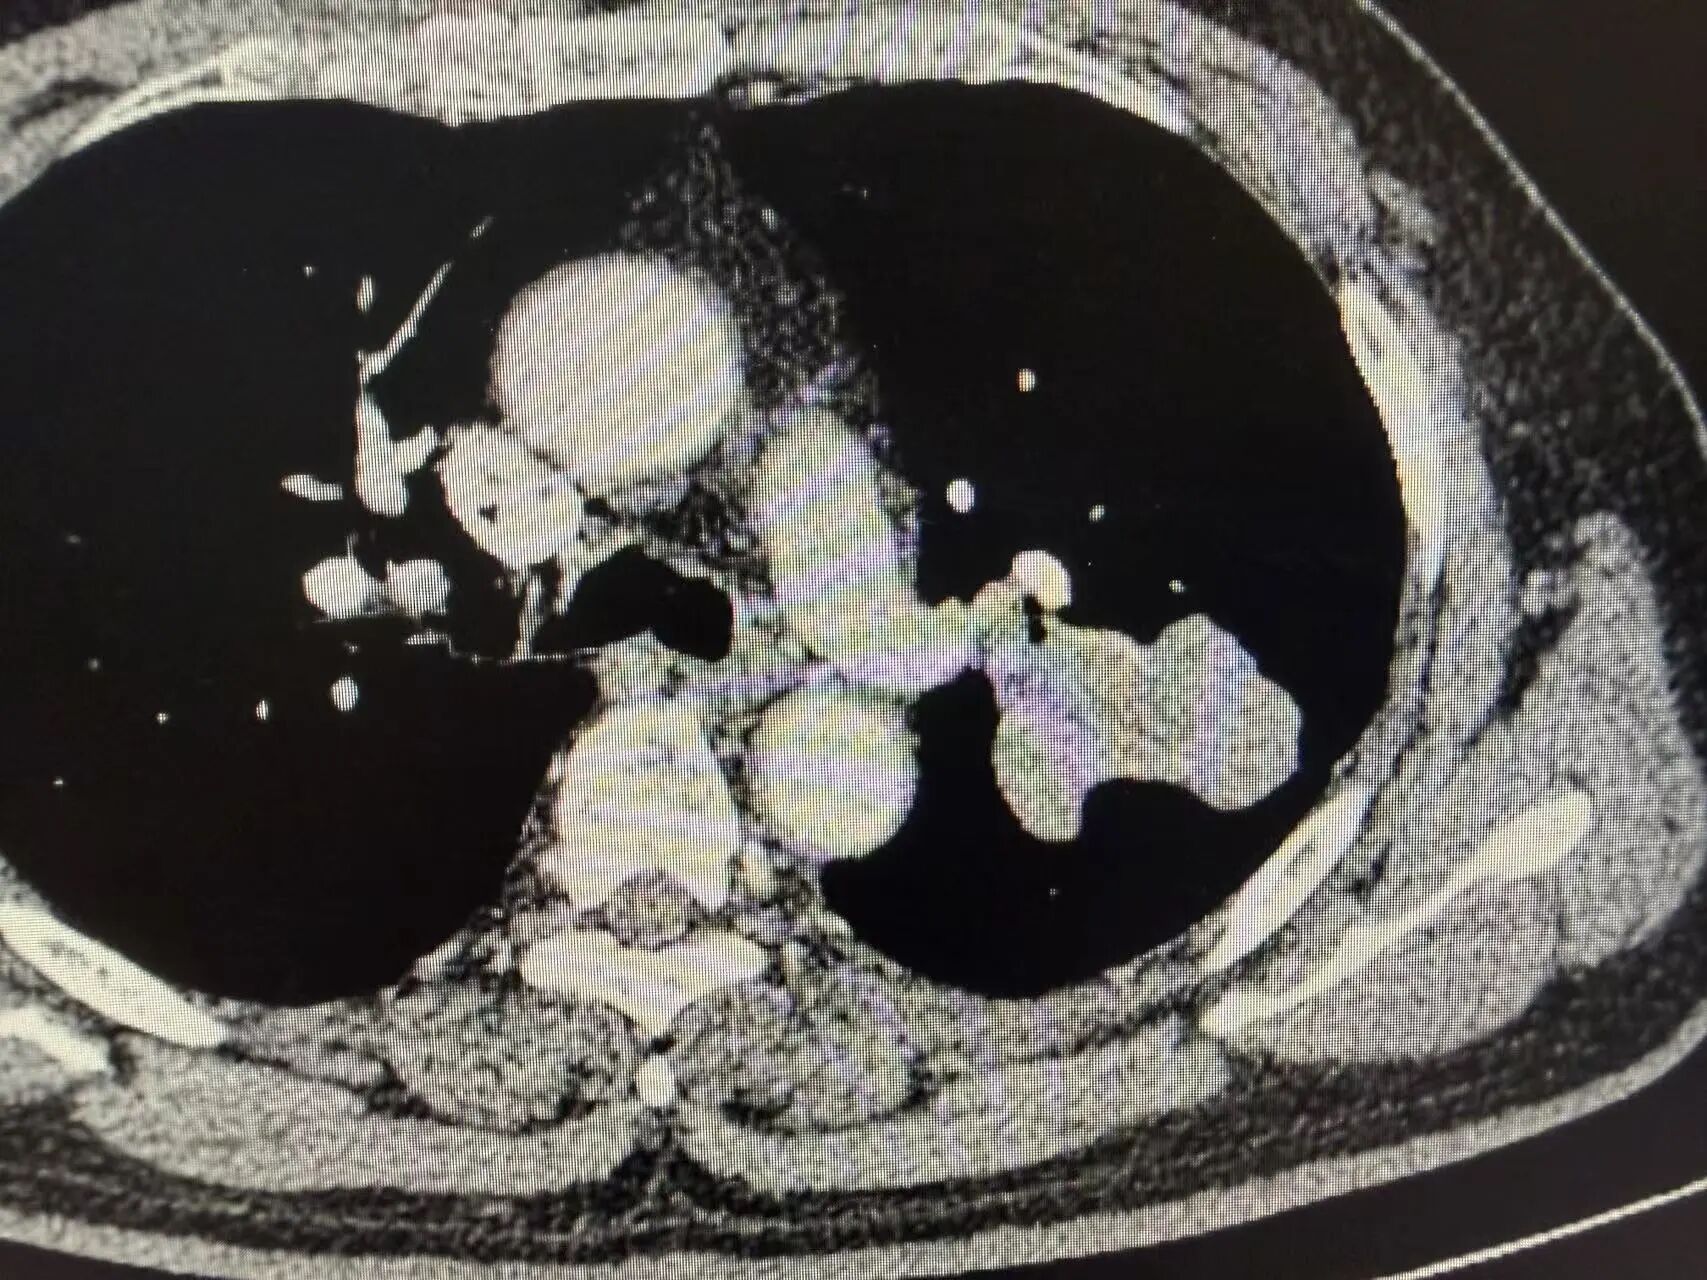

复查胸部CT显示:原左上肺肿瘤病灶显著缩小,肿大的肺门淋巴结基本恢复正常大小,肿瘤评估达到显著临床缓解,手术时机成熟

新辅助治疗后CT影像